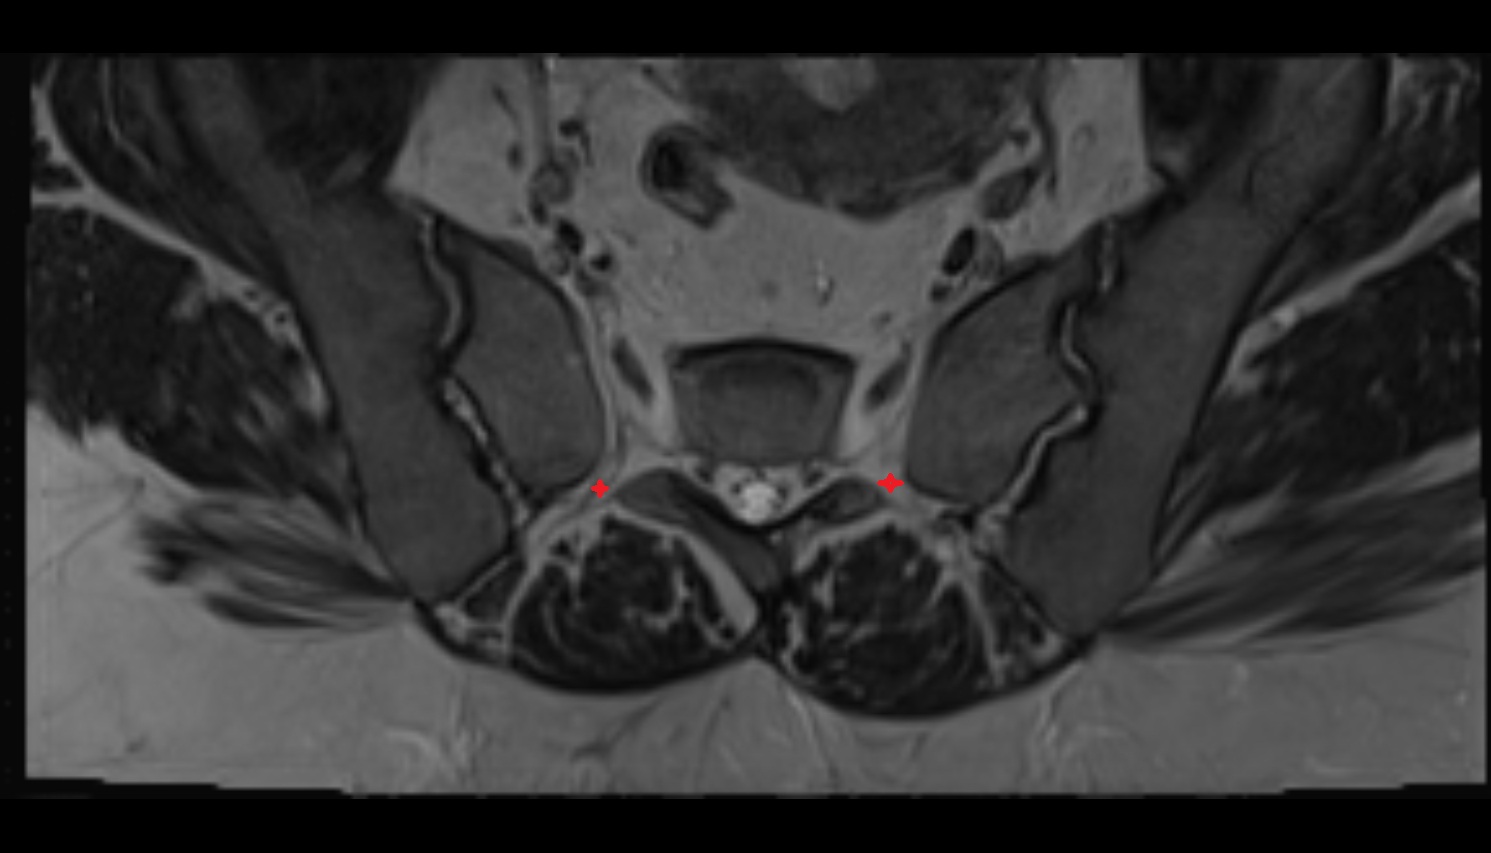

- Peripheral zone of prostate

- Anterior Fibromuscular Stroma of prostate

- Central zone of prostate

- Transitional zone of prostate